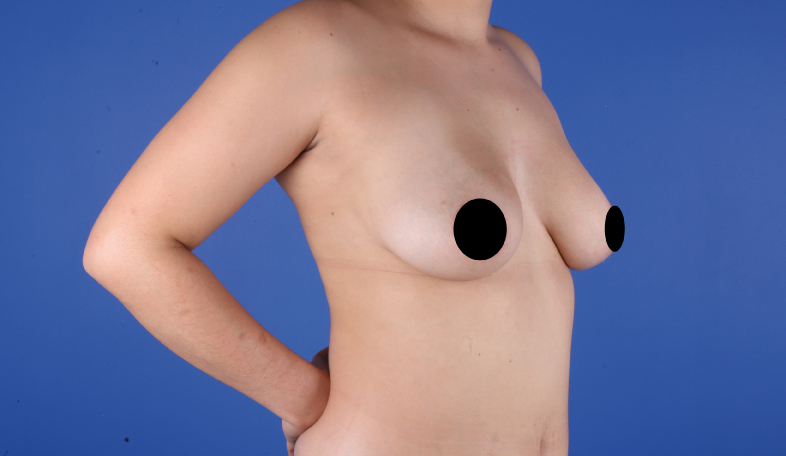

Es una ayuda diagnóstica complementaria que se utiliza para capturar imágenes de cualquier parte del cuerpo, aplicando técnicas que permitan obtener fotografías proporcionales, detalladas y nítidas; empleadas para medir, trazar, predeterminar y planear un proceso quirúrgico.

Es utilizada para crear imágenes del cuerpo humano, o partes de él, con propósitos clínicos que buscan revelar, diagnosticar y planear un tratamiento médico.